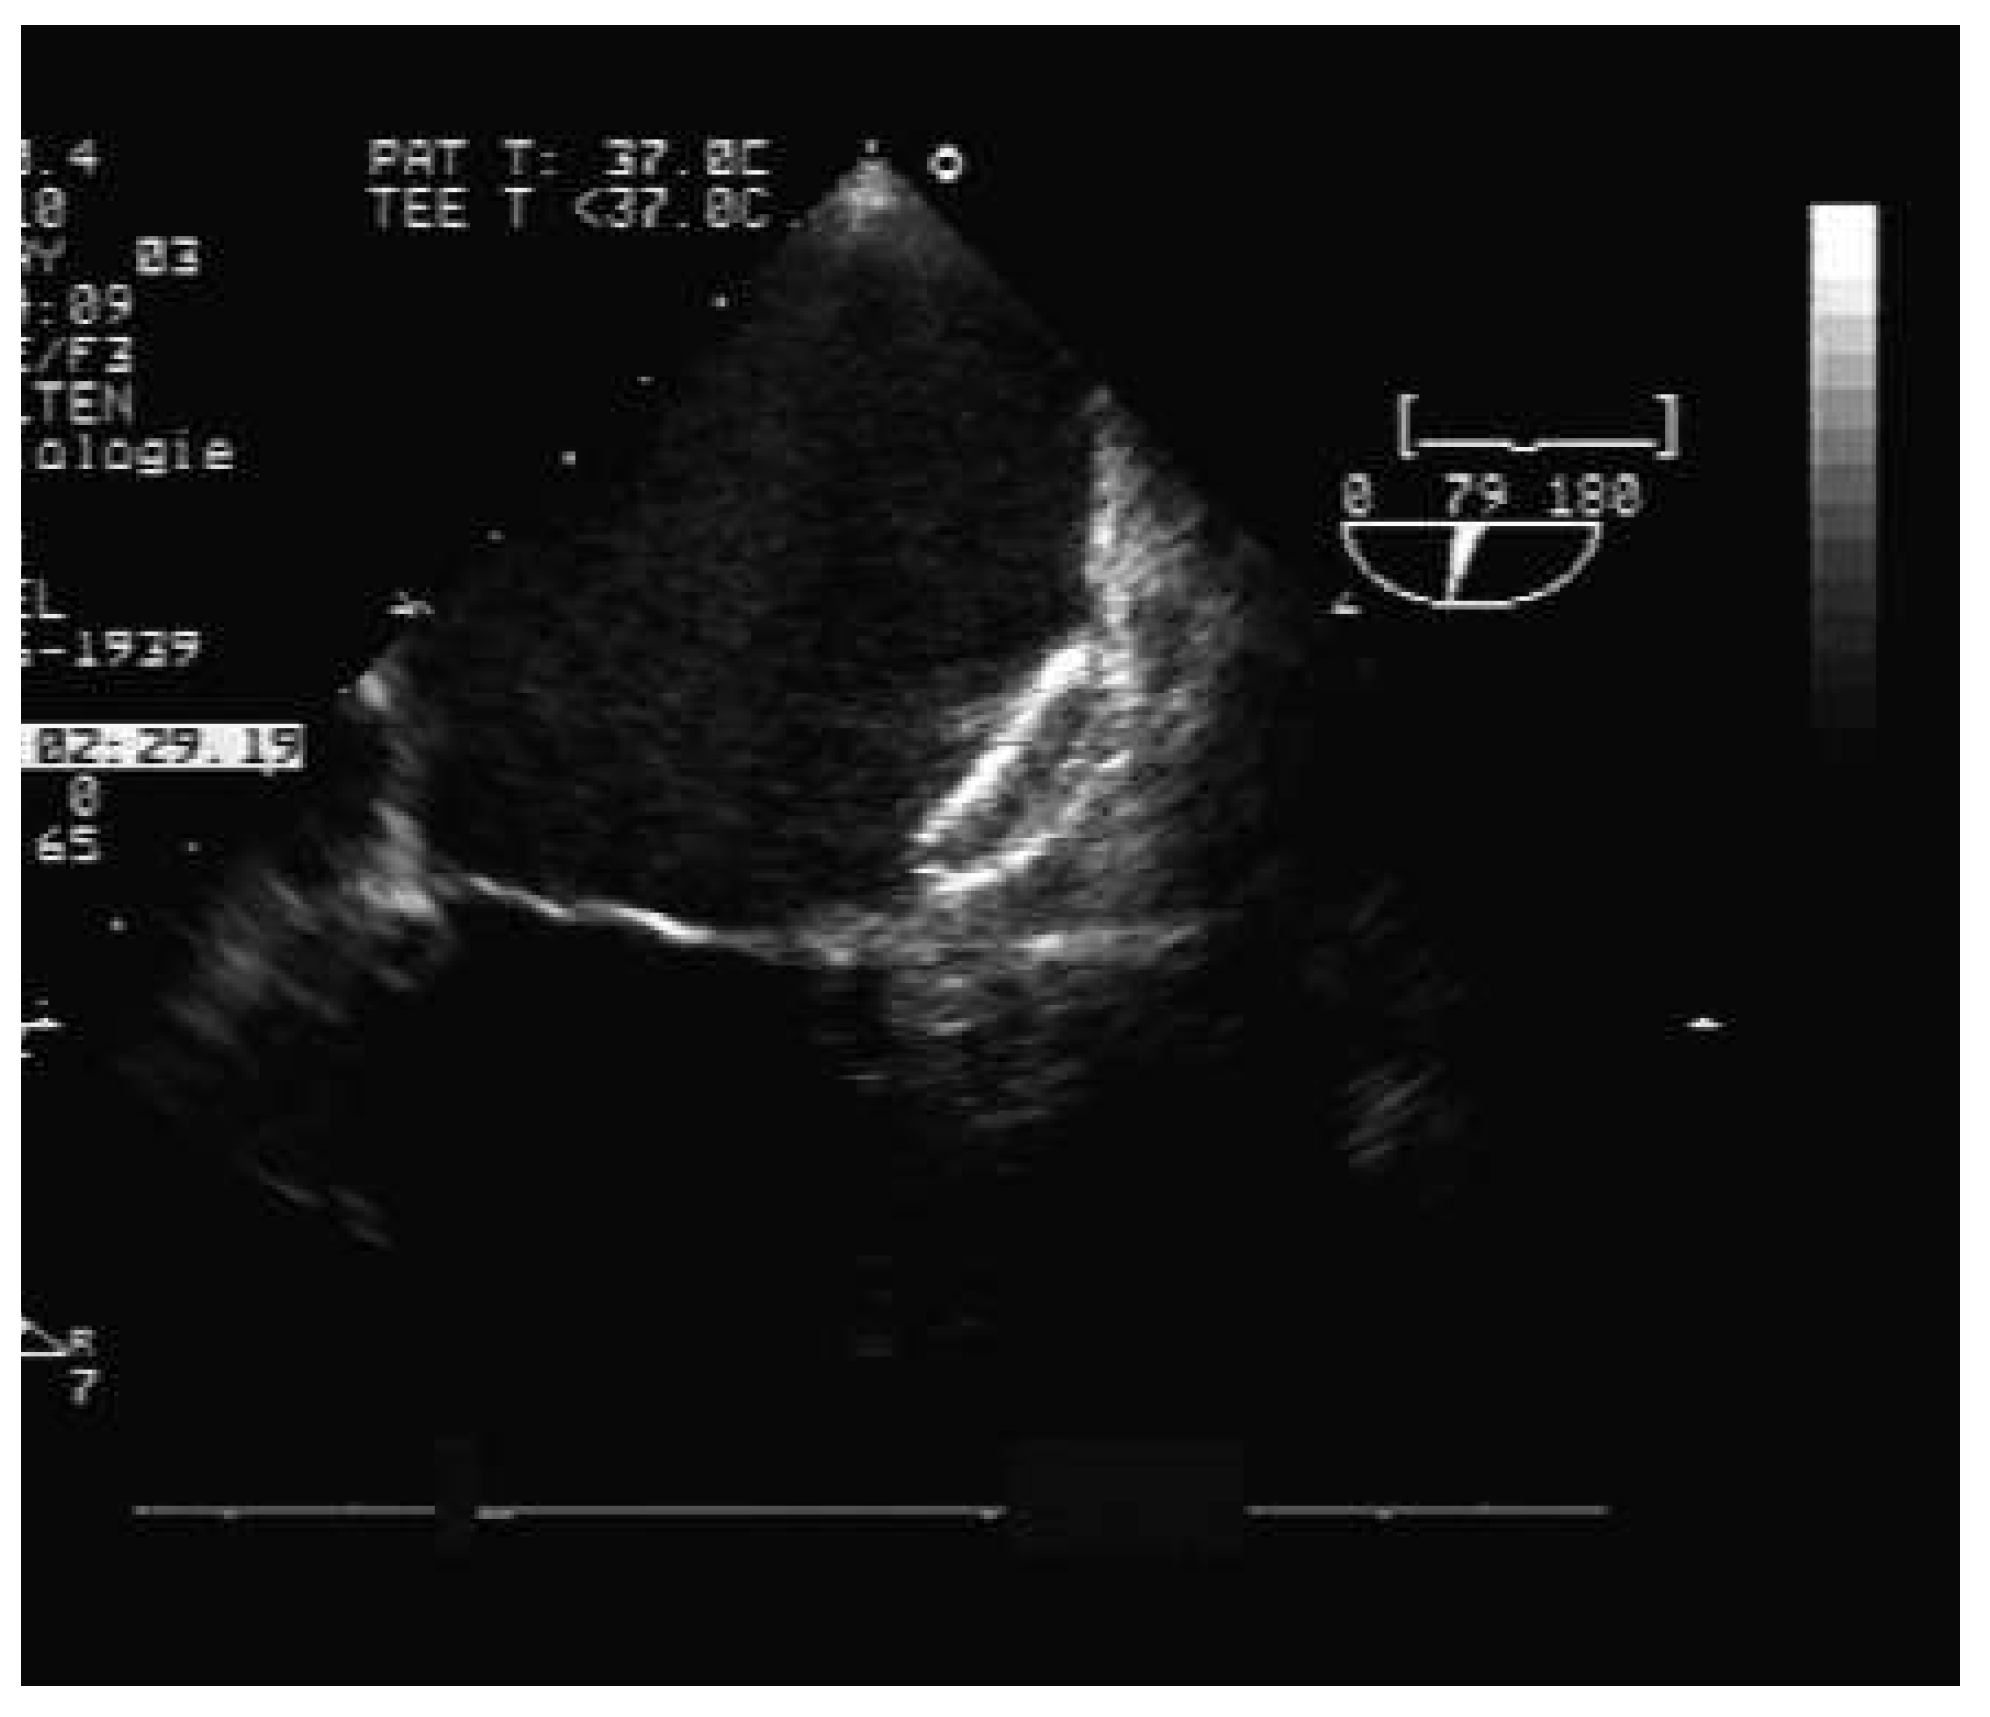

Techniques of left atrial appendage occlusion

Percutaneous technique for left atrial appendage occlusion